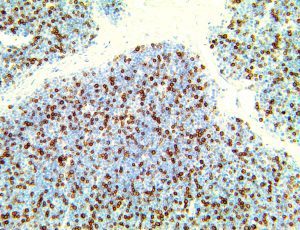

It is the ICU physician who is most likely to witness one of the deadliest manifestations of the abnormal immunological response, the cytokine storm syndrome (CSS). This response is also referred to by some as the cytokine release syndrome (CRS). CSS is characterized by continuous activation and expansion of macrophage and lymphocyte populations, which secrete large amounts of cytokines, causing the cytokine storm. This massive cytokine release is akin to hemophagocytic lymphohistiocytosis (HLH) disease, a syndrome characterized by initial unchecked and persistent activation of cytotoxic T lymphocytes and NK cells.

Clinical and laboratory manifestations of HLH include fever, enlarged liver and/or spleen, neurologic dysfunction, coagulopathy, liver dysfunction, cytopenias (i.e., low levels of erythrocytes, leukocytes, and/or platelets), hypertriglyceridemia, hyperferritinemia, hemophagocytosis, and eventually diminished NK cell activity as the immune system becomes progressively paralyzed. HLH can be familial (primary HLH) or secondary to another disease process (sHLH), such as rheumatic disease, in which it is referred to as macrophage activation syndrome (MAS, characterized by elevated ferritin).